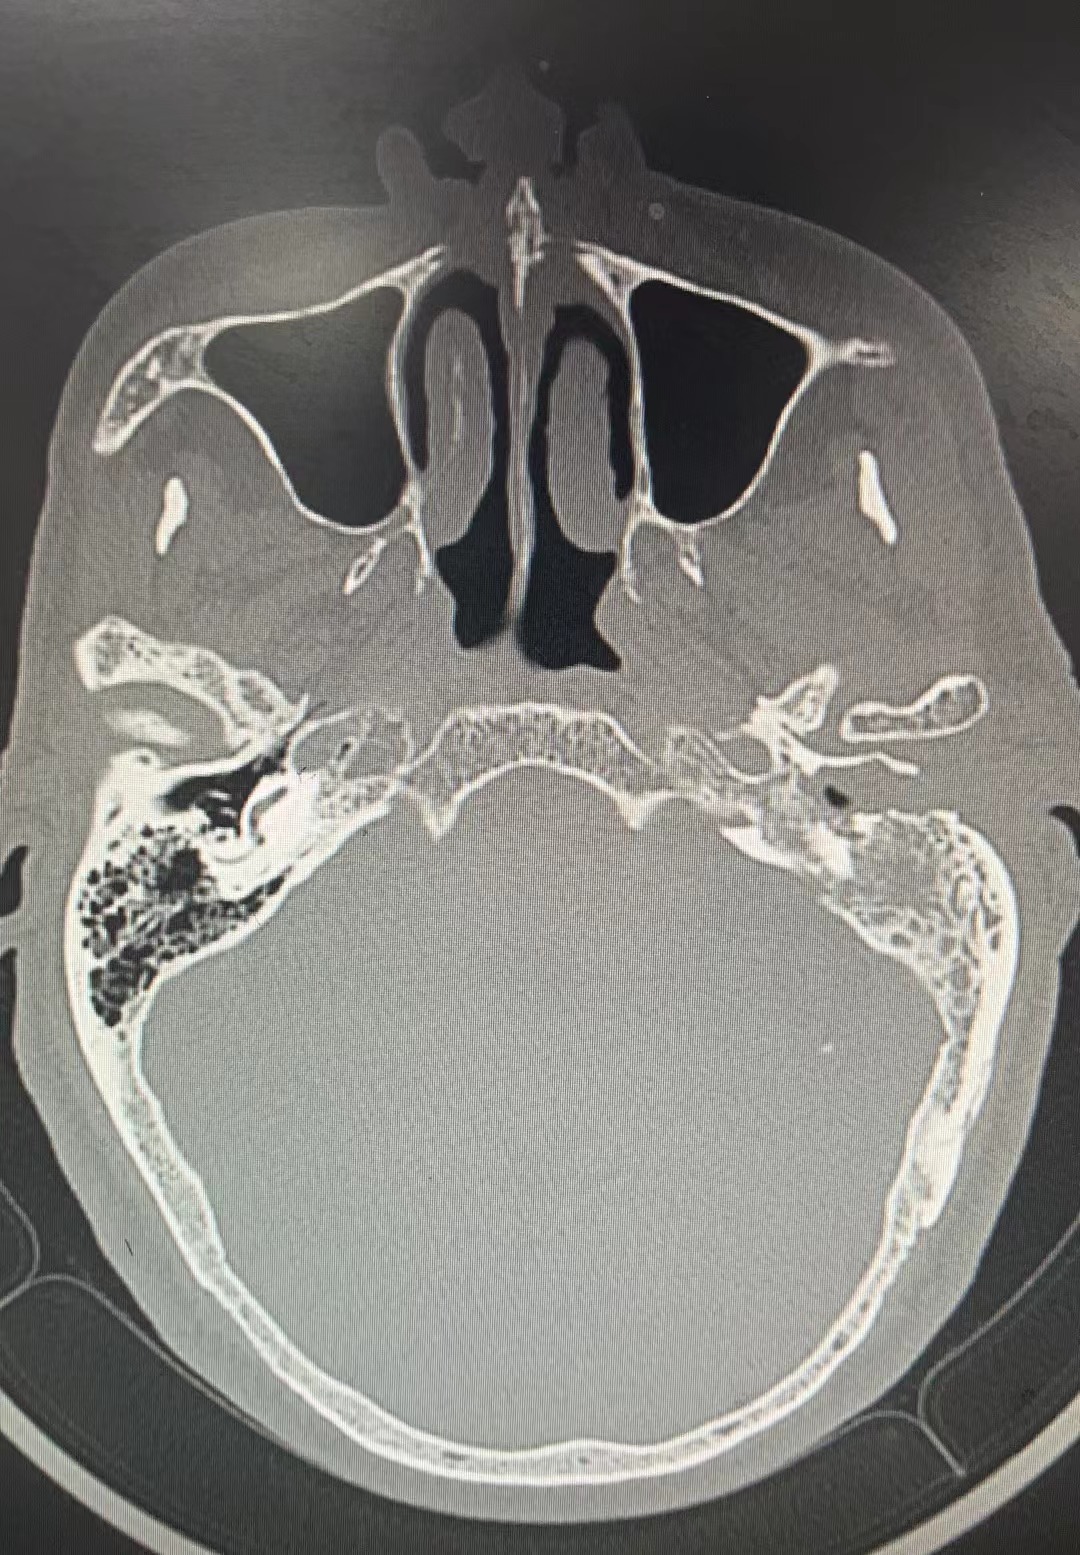

入院后积极完善相关检查,外耳道分泌物培养显示MRSA感染,影像学检查示左侧中耳、乳突、外耳道及颞骨岩部均异常信号,考虑肿瘤复发并破坏左侧颞骨及枕骨,其余全身检查未见癌转移。

术前CT